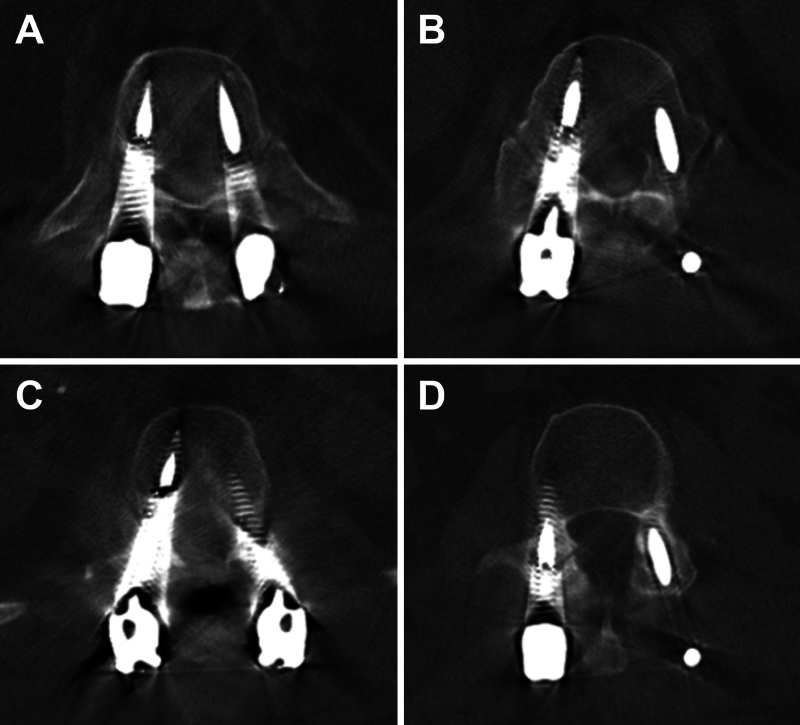

Background: Metallic implants can cause imaging artifacts on CT and MRI. Although metal artifact reduction (MAR) techniques have enhanced imaging clarity, they can also lead to distortions that may resemble complications such as hardware fractures. The false appearance of fractured hardware, or "pseudofractures," can distort imaging interpretation and result in unnecessary revision surgery.

Observations: A 65-year-old male sustained a T12-L1 fracture extending through the disc space with ligamentous interruption after a bicycle accident. The patient underwent T11-L2 posterior fusion with pedicle screws and was discharged in a thoracolumbar sacral orthosis brace after an uncomplicated postoperative course. Concerns about brace compliance prompted imaging, which demonstrated screw fractures and led to discussion of revision procedure. Repeat imaging revealed that these were artifacts, not hardware failure. No revision was needed and the patient continued to recover.